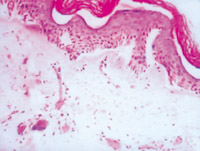

5-2-3 傷后第3天,表皮細(xì)胞空泡化,真皮淺層膠原纖維玻璃樣變,真皮內(nèi)散在炎細(xì)胞浸潤(rùn)  HE×100